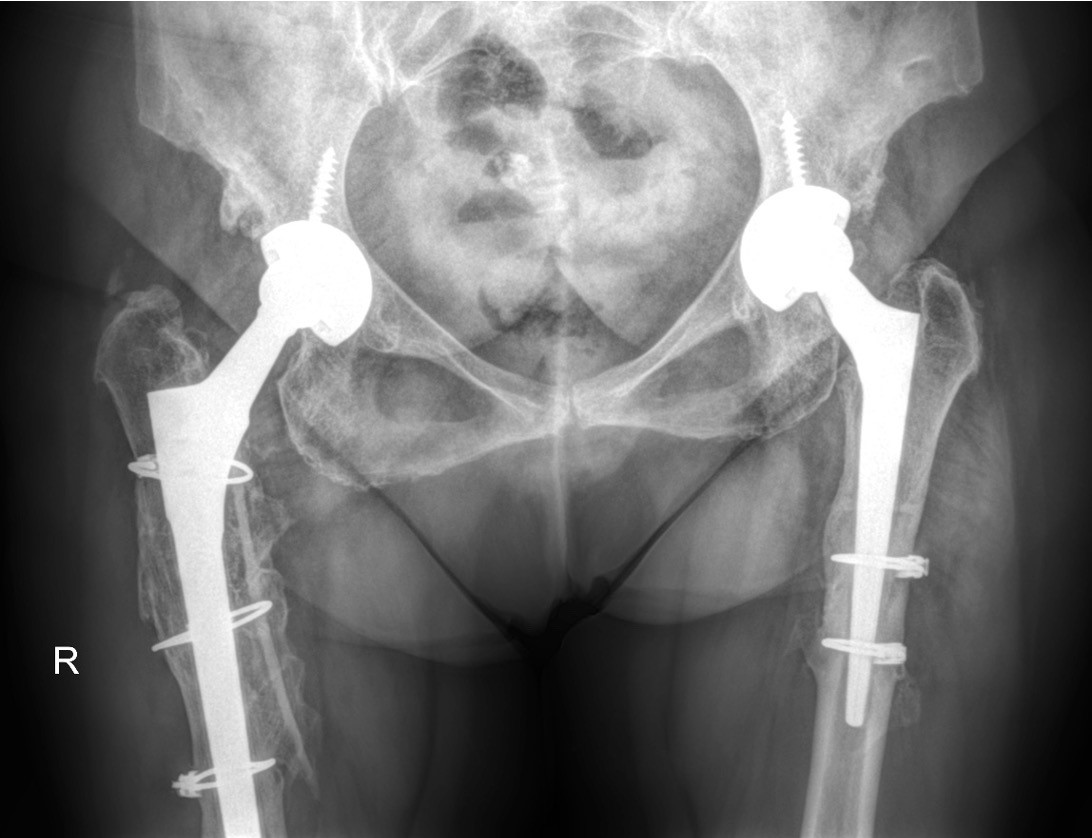

Συχνά, ιδιαίτερα στα υψηλά εξαρθρήματα, η δυσκολία να τοποθετηθεί η κοτυλιαία πρόθεση στην ανατομική θέση αντιμετωπίζεται με οστεοτομίες του μηριαίου που και αυτή είναι μία απαιτητική χειρουργική διαδικασία.

Ο προεγχειρητικός σχεδιασμός μέσω την αξονικής τομογραφίας του το ρομποτικό σύστημα ΜΑΚΟ προσφέρει, καθοδηγεί με απόλυτη ακρίβεια διεγχειρητικά να τον χειρουργό να τοποθετήσει τις προθέσεις, ιδιαίτερα αυτή της κοτύλης στην ανατομική θέση και σωστά προσανατολισμένη, απαραίτητη συνθήκη για να επιτευχθεί μία σταθερή αρθροπλαστική και να ελαχιστοποιηθούν τα μετεγχειρητικά εξαρθρηματα της πρόθεσης.

Σημαντική επίσης είναι η καθοδήγηση που λαμβάνει ο χειρουργός από το ΜΑΚΟ να αποκαταστήσει χωρίς επιπλοκές την ανισοσκελια η οποία όπως τονίστηκε συνοδεύει το συγγενές εξάρθρημα του ισχίου